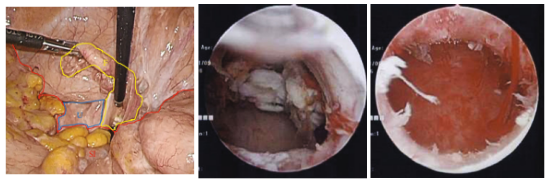

因此,进行了腹腔镜辅助下宫腔镜子宫切除术的诊断和治疗。首先,通过腹腔镜观察腹腔(图3)。放疗后子宫粘连严重,活动性差。用双极电凝器封闭双侧输卵管。其次,宫颈扩张后,宫腔镜下观察宫腔(图4)。子宫内膜萎缩和两个肿瘤被证实。用电动手术刀切除肿瘤并将其排出子宫外(图5)。对肿瘤残端及子宫内膜的其他部位进行活检。腹腔镜监测宫腔镜手术以防止并发症。病理诊断为子宫内膜息肉,残端阴性。术后随访2年,无肿瘤复发。

图3. 腹腔镜检查结果。子宫(U)因放射疗法而萎缩,并牢固附着在小肠(SI)上。活动性非常差。可以检测到输卵管(F)

图4. 宫腔镜检查结果。在子宫腔中检测到两个肿瘤

图5. 宫腔镜检查结果。在手术结束时,子宫腔是干净的